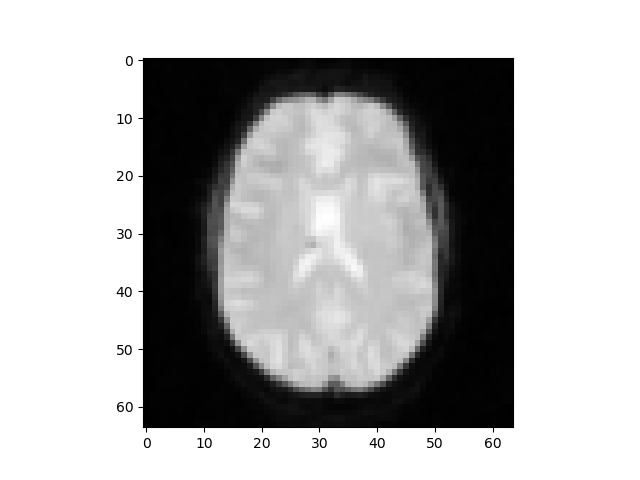

19 participants completed 600 trials (five runs of 120 trials); each run resulted in 787 medical 2D images which were converted into 3D datasets. The AFNI (Analysis of Functional Neuroimages) data is composed of two files (per trial per participant) containing the voxel numerical values, spatial characteristics of each voxel, and statistical information for each sub-brick. We will merge the files into the NIFTI file which encapsulates both metadata and the actual image data as the final dataset for machine learning in Python.

Figure 1

Experimental Design from Dunovan & Wheeler (2018). Each trial condition is depicted along with the breakdown of the cues in each trial.